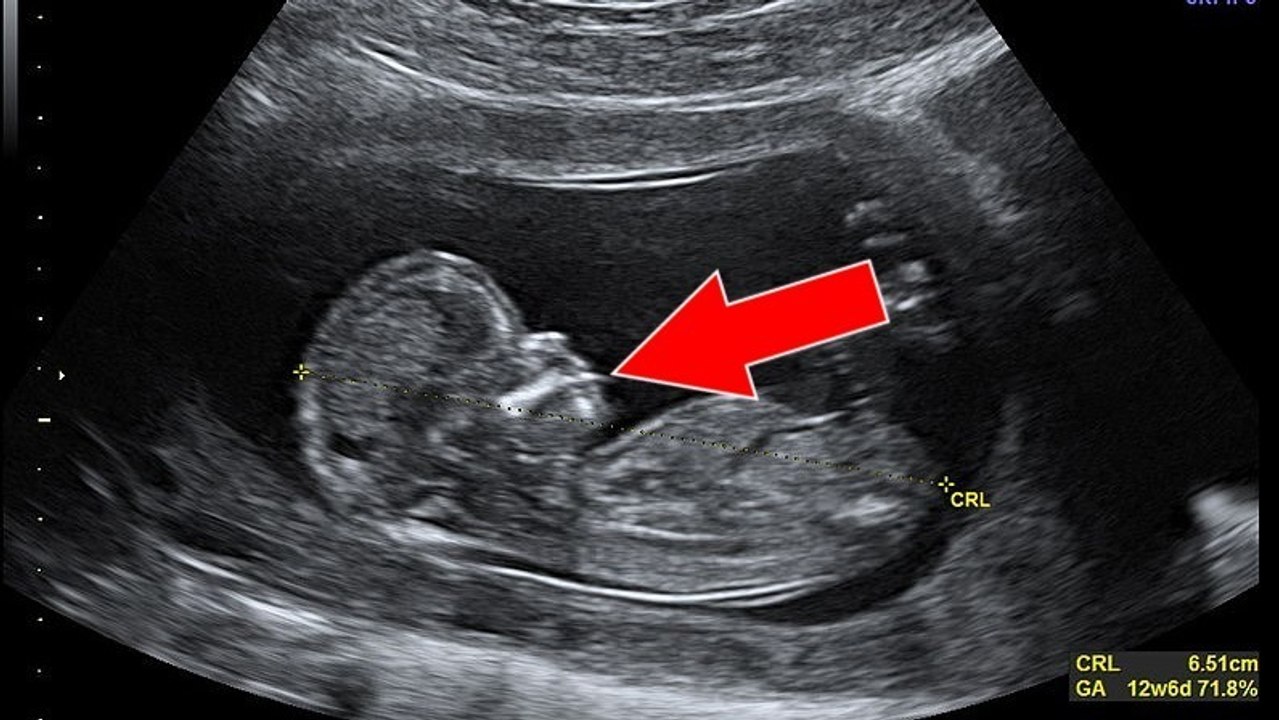

Diese Frau erwartet ihr viertes Kind. Was sie auf dem Ultraschall entdeckt, ist allerdings ein Schock!

Diese schwangere Frau macht eine unglaubliche Entdeckung auf ihrer Ultraschallaufnahme

Eine schwangere Frau freut sich auf Baby Nummer 4. Doch dann erfährt sie, wie viele Babys sie wirklich im Bauch hat!